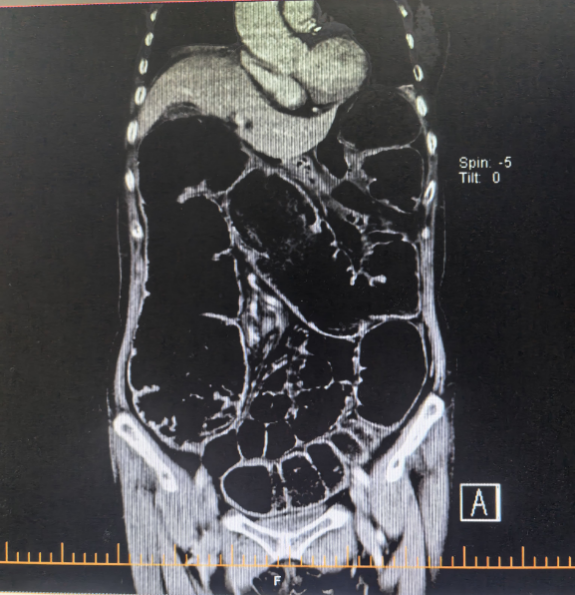

治療前腹CT示腸腔明顯擴張 治療后立位腹平片示腸道梗阻較前明顯緩解

近日,在北京中醫(yī)藥大學(xué)東方醫(yī)院二七院區(qū),一場與時間賽跑的生命救援悄然上演。一位老年患者因“腹部脹痛1月,且近3日無排氣排便”前來就診。經(jīng)門診腹部 CT 檢查,結(jié)果顯示為低位腸梗阻,直腸上段占位可能性極大。